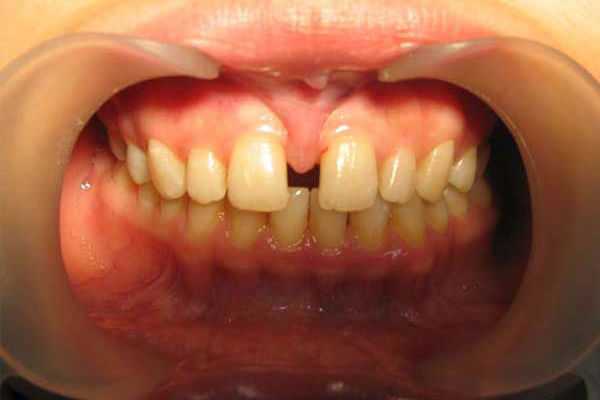

- Диастема, или щель между передними зубами. Дело даже не в заметном дефекте. Уздечка между зубами препятствует правильному положению зубов, из-за чего они травмируются и разъезжаются.

- Образуется диастема (промежуток между передними резцами) из-за того, что уздечка тянет верхнюю десну, не позволяя центральным резцам сомкнуться.

У грудных детей с короткой уздечкой верхней губы могут возникать проблемы кормления, которые являются причиной беспокойства младенца, и сильно утомляют мать. После прорезывания зубов дефект уздечки провоцирует появление неэстетичной щели между зубами.